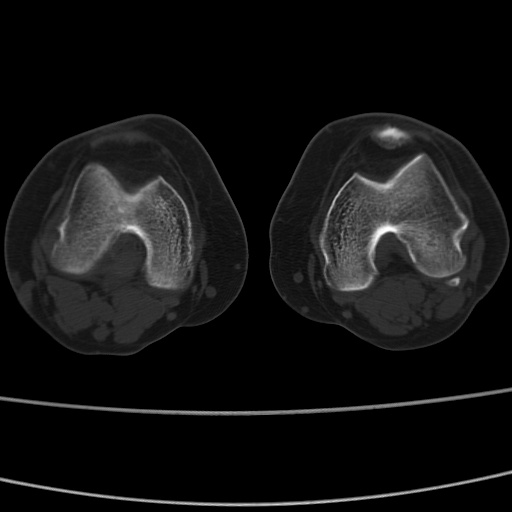

女性,50岁。【请提供患者临床症状体征】

右膝关节退行性改变,关节游离鼠。

右膝关节退行性改变,滑膜黏液囊钙/骨化并游离。

右膝关节退行性改变